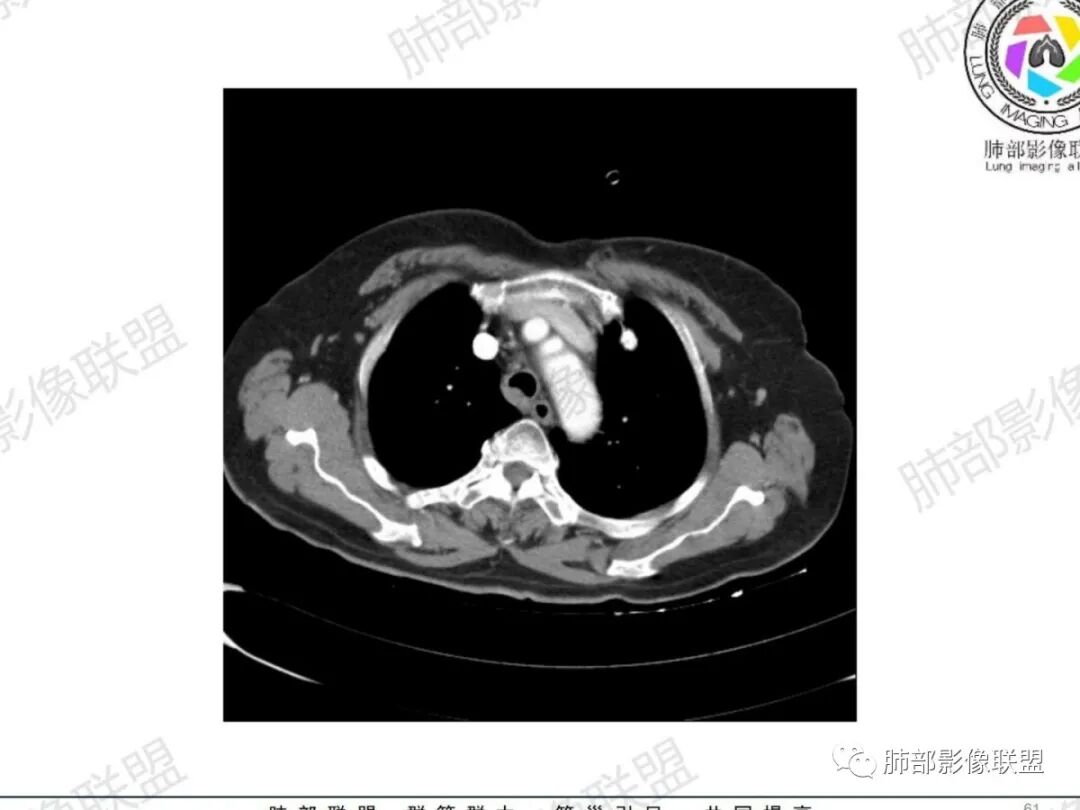

气管结节,不均匀明显强化,跨气管壁,老年女性,考虑恶性——原发:腺样囊性癌、鳞癌、类癌;转移:甲状腺癌?转移。强化部分与甲状腺基本一致,转移瘤可能性大。

主支气管腔内外见软组织肿块,密度不均,不均匀强化,腔内肿块边缘光滑,增强可见不均匀强化,病程长,考虑良性肿瘤性病变,支气管平滑肌瘤?甲状腺左侧叶结节,考虑甲状腺腺瘤或结节性甲状腺肿。

老年女性,慢性病程,反复咳嗽,胸闷2天,支气管内见新生物突向管腔,增强轻中度强化,无明显坏死,左侧甲状腺内见低密度结节,增强示低密度灶内结节状明显强化结节,肺部多发结节,考虑转移,鉴别粘液表皮样癌,腺样囊性癌

增强层面仅有两个,看似比较均匀。直接支气管镜搞定

宽基底,腔内外,看似边界清楚、光滑, 但是附近气管壁增厚,还是首先要考虑恶性,附近淋巴结也不太放心,因为强化明显

甲状腺结节边界不太清楚,但是窗宽窗位不太理想,需要调至最佳状态观察才合适

病理类型:甲状腺如果是恶性的,还是要警惕转移瘤;原发的:倾向于恶性,老年女性,表面光滑, 鳞癌几率比较低;腺样囊性癌确实要考虑